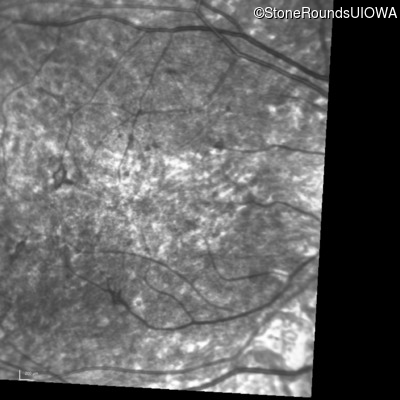

Infrared Fundus Photograph - Left - 5/180

Exemplar

Infrared Fundus Photograph - Left - 5/200